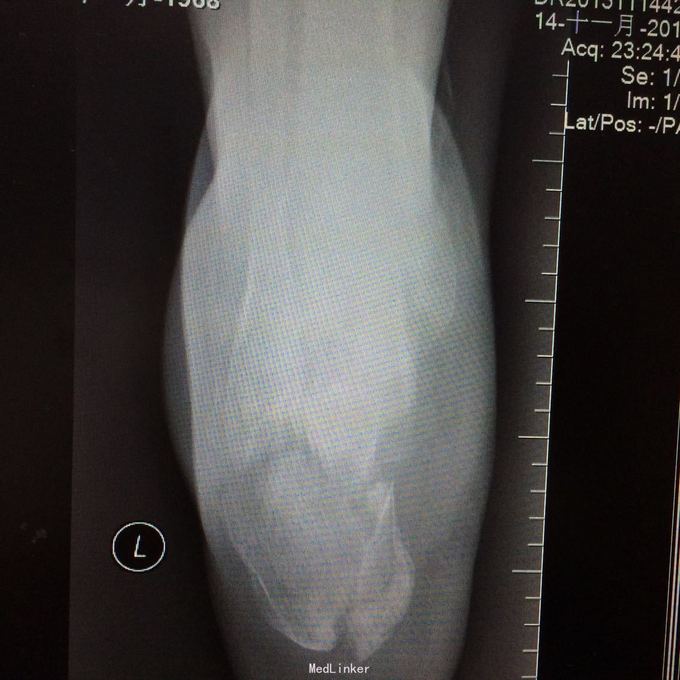

患者某某,男,49岁,因“高处坠落致全身多处疼痛、肿胀、流血2小时 1、男性壮年患者。 2、缘患者于2小时前因高处坠落致左肘、左手、右手、头面部、左胸,左足等多处受伤,即觉左肘部疼痛、活动困难、流血;左手、头面部伤口疼痛、流血;右手、左胸,左足部等处疼痛、肿胀。由家属、同事送往我院就诊,经行X线检查示:左肱骨远端粉碎性骨折,左肘关节半脱位;左手第4、5掌骨远端骨折;右手第1远节指骨基底部、第3、4远节指骨骨折,第5中节、远节指骨骨折;左跟骨粉碎性骨折。CT示:鼻中隔骨折;右侧第3--7肋骨折。急诊科予清创包扎止血,为作进一步诊治而收入院。患者受伤以来,患者精神好,无呼吸困难,无恶心、呕吐,无头晕,无面色苍白,无双下肢麻木、无力,无大小便失禁。 3、查体:T36.8 ℃ P 76次/分 R20 次/分 BP104/67mmHg。神清合作、应答切题、全身皮肤粘膜无黄染、浅表淋巴结无肿大。头颅五官无畸形,左眉弓处见一长约2cm伤口,活动性出血,巩膜无黄染,双侧瞳孔等大等圆,直径 3 mm,对光反射灵敏。鼻梁有一长约3cm纵行伤,深及皮下,伴有活动性出血;下唇部见一1*1cm组织缺损,伴活动性出血.颈软,无抵抗,气管居中,甲状腺无肿大,胸廓无畸形,右侧胸部局部压痛明显,胸廓挤压征阳性;心前区无隆起,双肺叩诊清音,呼吸音清,无干湿性罗音。心率76次/分,律齐有力,各瓣膜区无病理性杂音。腹平,腹肌软,全腹压痛、无反跳痛,肝脾肋下未及,双肾区无叩痛,无移动性浊音,肠鸣音存在,4-6次/分。脊柱、骨盆无压痛,四肢检查详见专科情况,其余肢体检查正常。双下肢生理反射存在,病理性反射未引出。

4、专科情况:左肘部中度肿胀,呈短缩、成角畸形,局部皮肤活动性出血,局部压痛明显,纵向叩击痛,左肘部可扪及骨擦感,有反常活动,左肘部活动障碍。左肩峰至肱骨外上髁上臂长度较右侧短缩1厘米,左手掌尺侧轻度肿胀,无畸形,局部皮肤正常,局部压痛明显,可扪及骨擦感,无反常活动,左手指活动正常。左侧手指肌力Ⅳ级,有牵拉痛,左上肢手指末梢血运良好,感觉略差。右手拇指、环指及尾指局部皮肤组织撕脱,渗血明显;右手中指末端损毁,局部缺失。右手手指肌力Ⅳ级末梢血运良好。左足跟部肿胀明显,局部皮肤正常,局部压痛明显,纵向叩击痛,左足跟部可扪及骨擦感,左足趾肌力Ⅳ级,无牵拉痛,左足趾末梢血运及感觉良好。 5、辅助检查:本院2015年11月14日X线检查示:左肱骨远端粉碎性骨折,左肘关节半脱位;左手第4、5掌骨远端骨折;右手第1远节指骨基底部、第3、4远节指骨骨折,第5中节、远节指骨骨折;左跟骨粉碎性骨折。CT示:鼻中隔骨折;右侧第3--7肋骨折;左下肺挫伤。

1、左肱骨远端粉碎性开放性骨折;2、左肘关节半脱位;3、左手第4、5掌骨远端骨折;4、右手第1、3、4远节指骨骨折;5、右手第5中节、远节指骨骨折;6、鼻部软组织挫裂伤;鼻中隔骨折;7、右侧第3--7肋骨折;8、左跟骨粉碎性骨折;9、左眉弓软质挫裂伤;10、左肺挫伤;11、脑震荡。 1.完善三大常规、PT四项、生化等各项常规检查; 2.完善CT检查,予抗破伤风、抗感染、镇痛、止血等对症支持治疗; 3.请口腔、耳鼻喉、眼科等相关科室会诊; 4.请示上级医师,指导下步治疗。 手术时间:2015年11月15日 术后诊断:左肱骨远端开放性粉碎性骨折 麻醉方式:全身麻醉 手术名称:左肱骨远端开放性粉碎性骨折清创缝合外固定架固定术 手术时间:2015年12月25日 术后诊断:左肱骨远端粉碎性骨折 麻醉方式:臂丛麻醉 手术名称:左肱骨远端粉碎性骨折切开复位内固定术 。 手术时间:2015-12-3 术后诊断:左跟骨粉碎性骨折;左肱骨远端粉碎性开放性骨折;左肘关节半脱位;左手第4、5掌骨远端骨折;右手第1、3、4远节指骨骨折;右手第5中节、远节指骨骨折;右足拇趾撕脱骨折并趾间关节脱位;鼻部软组织挫裂伤;鼻中隔骨折;右侧第3--7肋骨折;左眉弓挫裂伤;左肺挫伤;脑震荡。 麻醉方式:腰硬联合 手术名称:左跟骨粉碎性骨折切开复位钛板内固定术